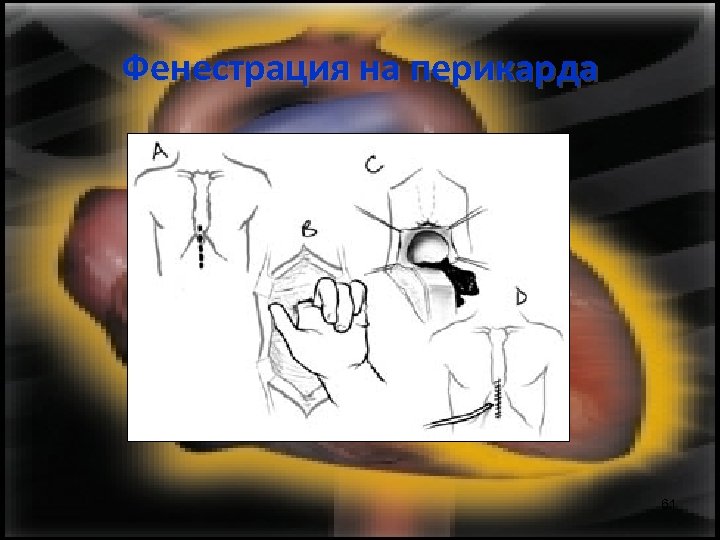

Фенестрация на перикарда 61